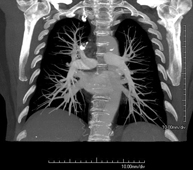

Prueba diagnóstica que consiste en el estudio de la aorta torácica (principal arteria del tórax) mediante el empleo de un equipo de TC (Tomografía Computarizada). Esta técnica requiere el empleo de contraste yodado, y proporciona imágenes de alta definición anatómica. El uso del TCMD (TC Multidetector) acorta el tiempo de exploración, disminuye la dosis de radiación y mejora la calidad de la imagen. Gracias a los múltiples detectores, en determinados estudios se puede acoplar la obtención de la imagen con el latido cardíaco, técnica que permite el estudio de la válvula aórtica y de la raíz de la arteria aorta (primeros centímetros), donde el latido del corazón suele provocar múltiples artefactos de movimiento. - Angio –TC Artèries pulmonars (estudi TEP, Tromboembòlia pulmonar)

Prova diagnòstica que consisteix en l'estudi de les artèries pulmonars mitjançant l'ús d'un equip de TC (Tomografia Computeritzada) per obtenir imatges bi i tridimensionals. En aquest estudi és imprescindible l'ús de contrast iodat que permet una millor definició anatòmica. Aquesta prova està principalment indicada en els casos de sospita de tromboembòlia pulmonar (TEP) per descartar o confirmar la presència de coàguls sanguinis a l'interior de les artèries. - TC Tòrax d'alta resolució